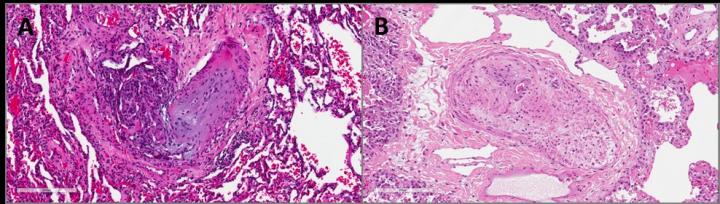

image: Obliterated pulmonary artery in pulmonary arterial hypertension showing fibrosis of the intima, hypertrophy of the media, and plexiform vasculopathy in A. Occluded pulmonary vein in pulmonary veno-occlusive disease showing fibrosis of the intima and hypertrophy of the media in B. Scale bars are labeled with 200 μm.

Patients with PH often experience narrowing, blockage, or destruction of lung blood vessels, a process referred to as vascular remodeling. In this study, researchers analyzed lung samples from patients with PAH, PVOD, idiopathic pulmonary fibrosis (IPF), chronic obstructive pulmonary disease (COPD), and healthy controls. As anticipated, patients with PAH had pathological changes predominantly in pulmonary arteries and arterioles, whereas samples from patients with PVOD were characterized by alterations of the post-capillary pulmonary vasculature (veins).